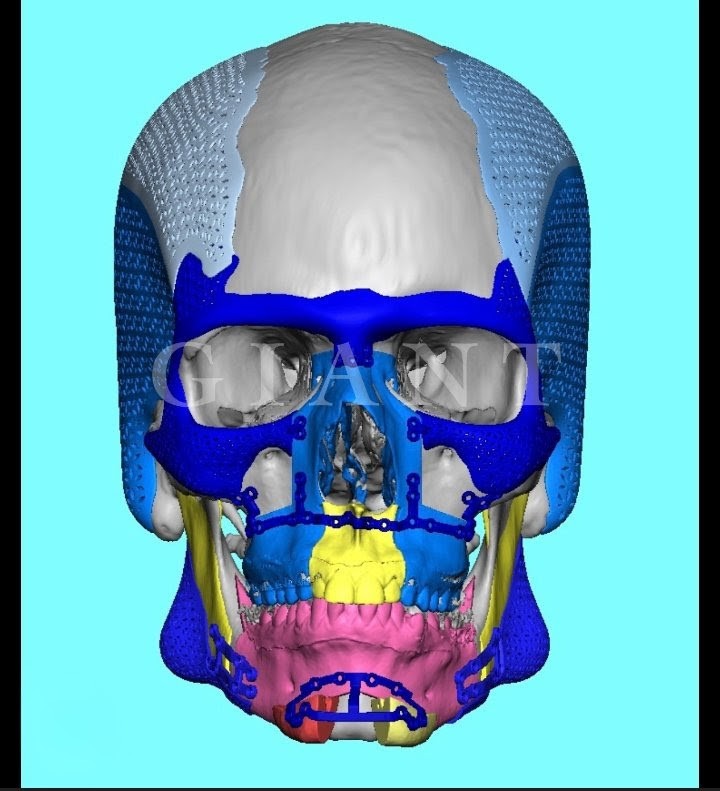

4. Full face custom implants

Hunter skull illusion

4. Full face custom implants

Hunter skull illusion